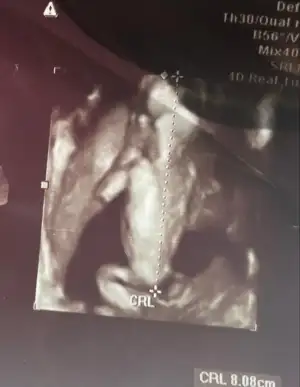

Sırtı dönük üç boyutlu tipe bakın ya😂küçük kurbağam🫶bu arada 16.haftadan önce cinsiyet açıklamayı sevmem ama erkek hani dedi yüksek ihtimalle eşim tekrar sorunca erkek gibi dedi💙

• 3889cb88-91d5-49d3-b3da-e0cec6ff8b57.webp

3889cb88-91d5-49d3-b3da-e0cec6ff8b57.webp

18,3 KB · Görüntüleme: 71